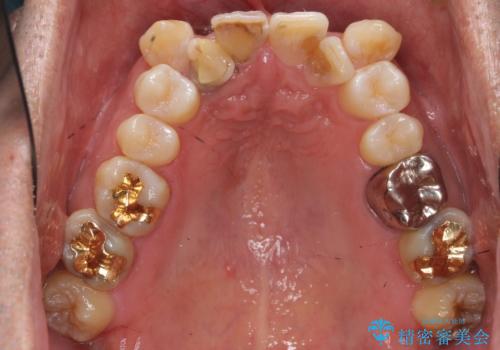

患者様の「できるだけ短期間で治療を終わらせたい、セラミックが入れられたら良いので大がかりなことはしたくない」とのご要望により、3Dシミュレーションを何度も行い患者様とのコンサルを重ね、上顎左右犬歯と左下2を抜歯して②のプランである補綴前矯正(インビザライン)を行うことにしました。

親知らずの抜歯はご希望されなかったため行いませんでした。

犬歯は歯根が長く寿命も長い歯で、咀嚼機能時も重要な役目を果たすため、基本的に矯正の便宜抜歯に選択する歯ではありません。(一般的には第一小臼歯もしくは第二小臼歯が選択されることが多いです)

本症例では、様々な抜歯パターンの3Dシミュレーションを行い患者様と相談を重ねリスクをご理解頂いた上で、患者様のご希望により例外的に犬歯の抜歯を行いました。

小臼歯の歯根長が長いことを治療前にレントゲンで確認し抜歯部位を決定しました。

側方運動時に大きな役割をもつ犬歯がないため、今後の定期健診で歯の状態を注意深く観察していく必要があります。